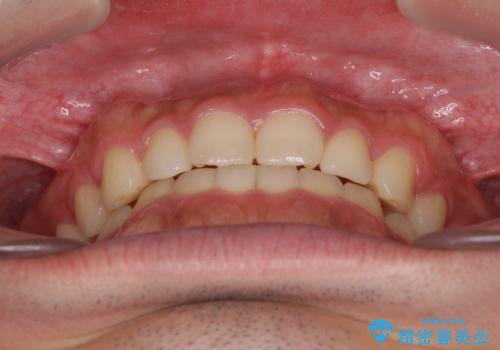

インビザラインによる、すきっ歯の改善

- 前歯がすきっ歯であることを気にして来院された患者様です。

下の前歯がほとんど隠れてしまうくらいの深い咬み合わせであったので、インビザラインを用いて、咬み合わせの高さを改善しながら隙間を閉じていくこととしました。

咬合力で上の前歯が前方に押し出されるようにして隙間ができていましたが、矯正治療により全て閉じることができました。

深い咬み合わせも多少改善され、隙間も閉じたことで、前方に出ていた前歯が引っ込んだため、口も閉じやすくなったとのことでした。